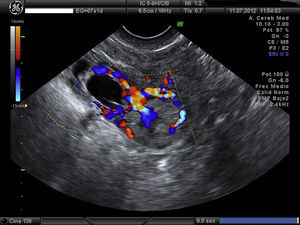

Embarazo actual de 7 semanas de amenorrea con sospecha de embarazo ectópico (EE) cornual. A la exploración, la paciente se encuentra estable, abdomen blando y depresible, sin signos de irritación peritoneal. Hemograma y bioquímica y coagulación normal y la β-HCG de 32.500mU/ml. Se confirma el diagnóstico de EE cornual derecho no accidentado por ecografía, presentando saco gestacional a nivel de cuerno derecho de 13mm con embrión de CRL 1,5mm y actividad cardíaca positiva (figs. 1 y 2). A la izquierda del saco, formación ecogénica mal delimitada de 18×18mm, muy vascularizada, compatible con trofoblasto (fig. 3). Anejos normales y no líquido libre.